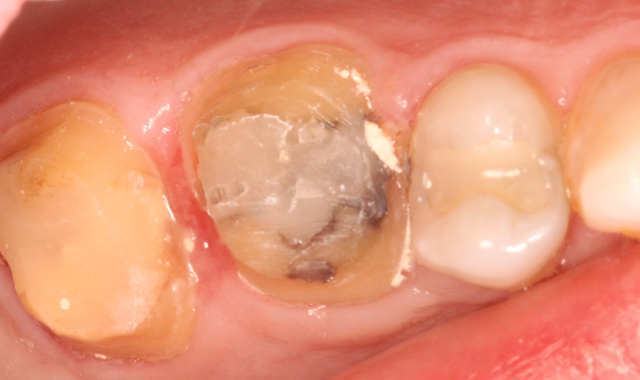

Fig. 3 Fig. 4

Both preparations were scrubbed with 2% chlorhexidine to remove any residual cement or debris. Both zirconia crowns were scrubbed with Ivoclean® (Ivoclar Vivadent) - a decontaminator - for 20 seconds, then thoroughly rinsed and air dried. A frosty internal surface appeared on both crowns.

Care was taken to directly load the crowns evenly with translucent SoloCem. SoloCem is a two paste system that is delivered in an automix syringe. It offers low shrinkage, high sheer bond strength, low water sorption, increased radiopacity and excellent bond strengths to dentin.

Because the monomers are already added to the cement formulation, the workflow was more efficient and certain of introducing no contamination. This is an important benefit, especially when performing quadrant dentistry (Fig. 5).